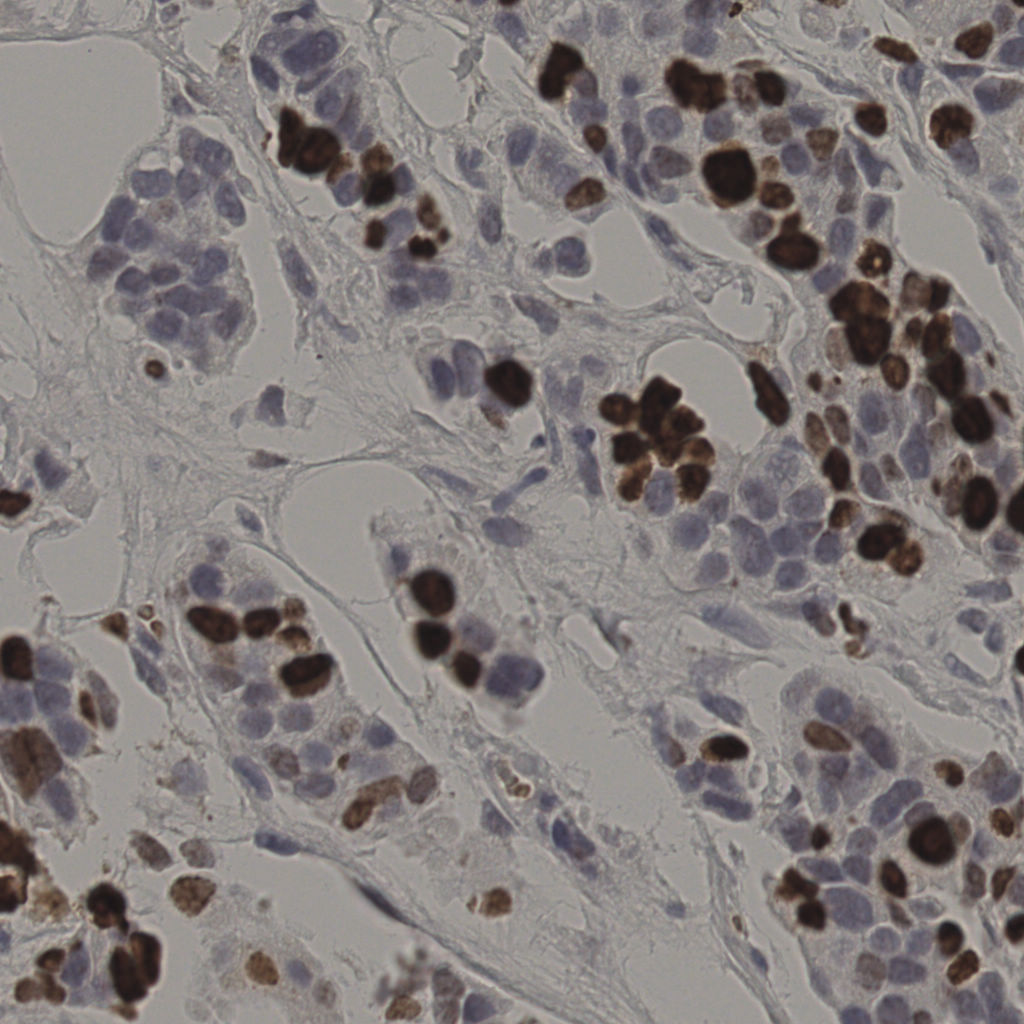

17.75%

Ki67 指数

阴 7986 阳 1723